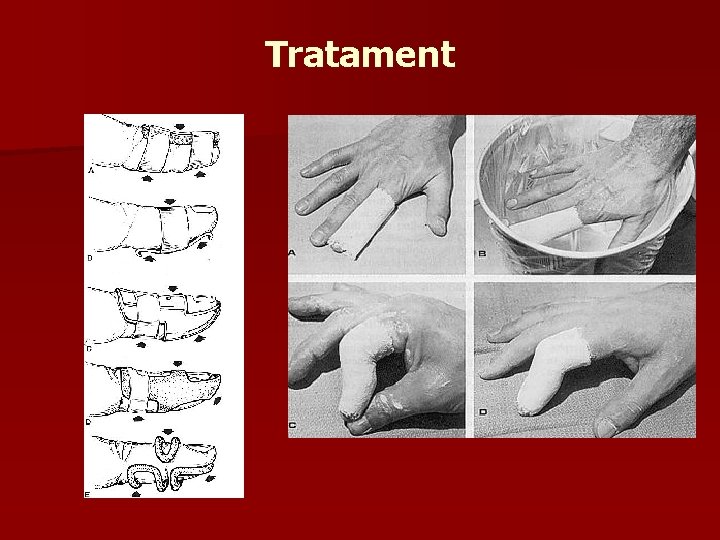

Tratament